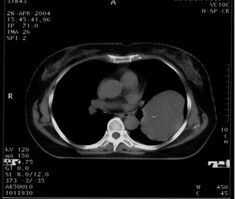

女,62歲。右大腿滑膜肉瘤,術(shù)后左下肺轉(zhuǎn)移,9.5×7.5cm。CT引導(dǎo)下瘤內(nèi)注射今又生,1×1012VP/次/周,共8次,結(jié)合60Gy放射照射。治療后腫瘤縮小48%,CT示瘤內(nèi)低密度區(qū)占50%以上,即腫瘤大部分壞死。

治療前

治療后